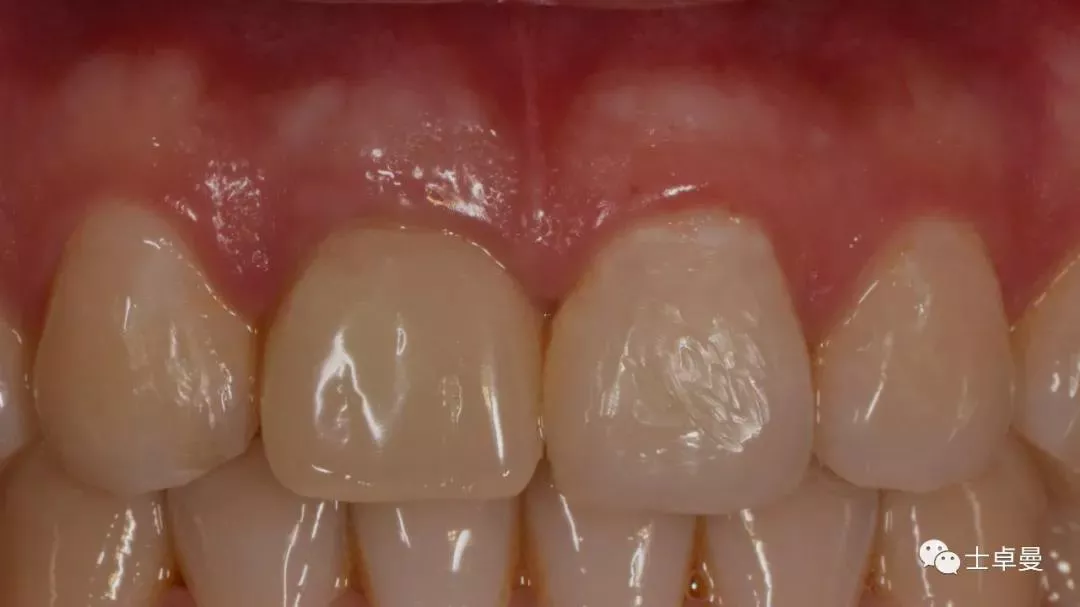

完成永久修复,骨弓轮廓、龈缘及龈乳头形态自然,可见牙龈点彩,修复体外形及色泽可,患者满意。

X线示,永久修复体已就位